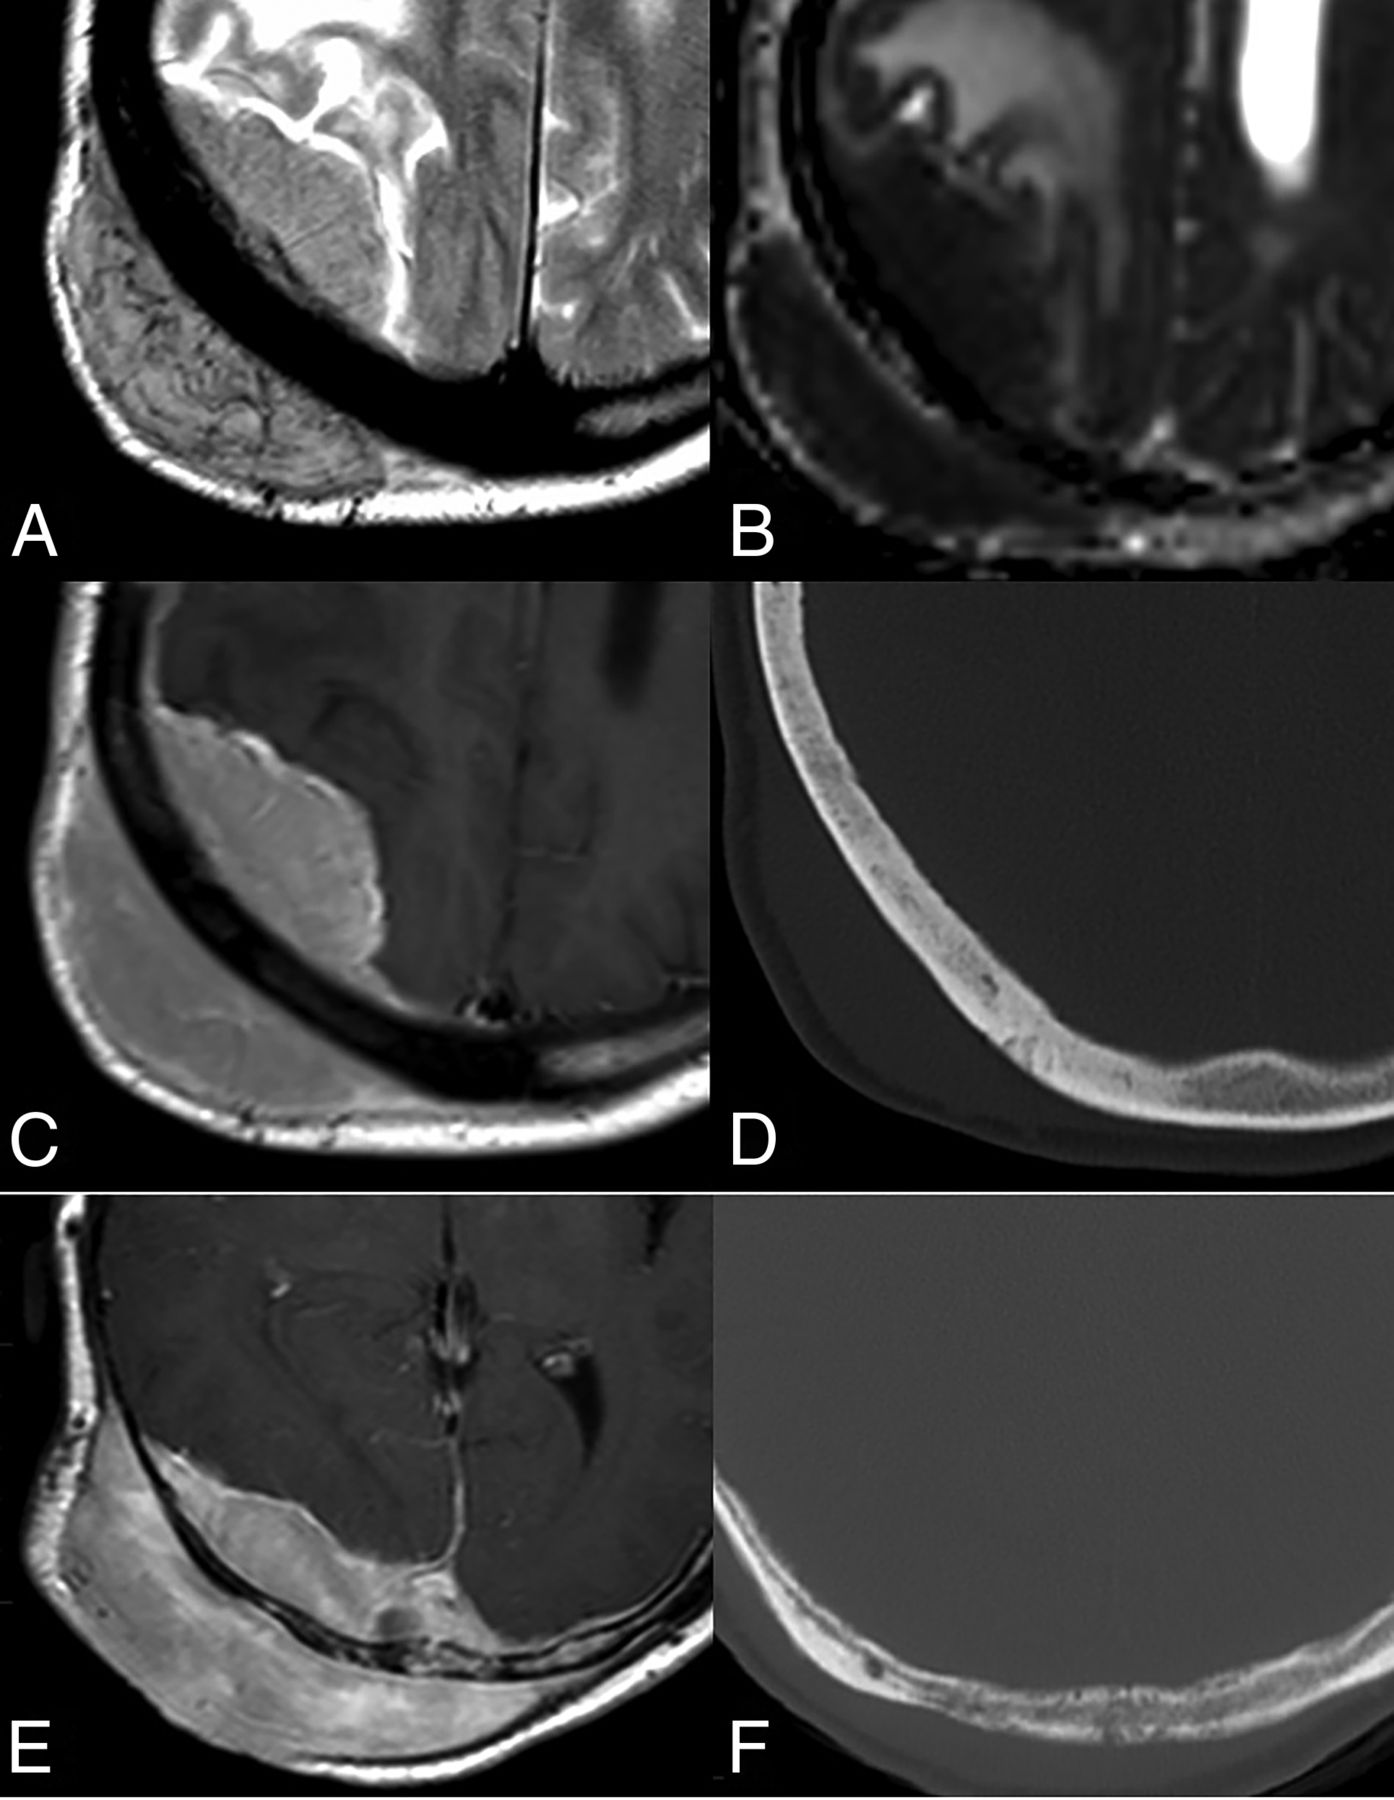

It usually appears as single or multiple (30%–35%) parenchymal lesions, located supratentorially (>80%), with a particular affinity for the basal ganglia, periventricular regions, midline, and corpus callosum (≈45%). It is also frequent in brain hemispheres (≈40%), rarely found in the posterior fossa, and exceptionally in the spinal cord (Fig 1).2 Associated leptomeningeal or subependymal enhancement is characteristic, but an exclusive presentation of the disease in this location may raise suspicion of secondary lymphoma. The typical perivascular histologic pattern also carries a characteristic perivascular enhancement on imaging (Fig 1). Parenchymal lesions are most frequently solid and homogeneous, but their presentation can range from well-defined expansive to ill-defined infiltrative lesions.2,5⇓-7,11

Primary DLBCLs of the CNS, EBV-negative. A–C: Usual deep, periventricular, corpus callosum, and midline location (A); a rare location in the posterior fossa (B); and exceptional in the spinal cord (C). D–G: Parenchymal lesions with associated characteristic leptomeningeal (D), subependymal (E), and perivascular (arrow, F) enhancement patterns. Histologic hematoxylin-eosin stain (original magnification ×20) shows highly cellular, perivascular accumulation of lymphoma cells (G). H–J: Mass lesion with ill-defined infiltrative (H) or well-defined expansive (I) margins. Hyperattenuated lesions on NCCT (J). K–N: Deep T2 hypointensity of a lesion (K) with a T2-blackout effect at b = 1000 image (L) but a low signal of actual diffusion restriction on the ADC map (M). Ki-67 proliferation index by immunohistochemistry (original magnification ×20) exceeding 90% (N).

Notably, these lesions are frequently hyperattenuating on NCCT,2,5⇓-7,11 which is important to keep in mind because CT is the first-line radiologic examination and suspicion at this point may lead to corticoid avoidance (Fig 1). If administered, corticoids can complicate subsequent imaging and histologic diagnosis.2,3,12

Regarding specific tumor MR imaging features, lymphoma typically appears hypointense on T2WI with marked diffusion restriction on DWI. Nevertheless, a T2-blackout effect consisting of a persistent hypointensity on b = 1000 images due to very low T2 signal may lead to misinterpretation. Thus, ADC map hypointensity might be more reliable than b = 1000 hyperintensity in assessing actual diffusion restriction.2,5⇓-7,11 NCCT hyperattenuation, low T2 signal, and diffusion restriction correlate with high cellularity on histology, with Ki-67 proliferation indexes usually above 90% (Fig 1).13

Historically, the presence of hemorrhage or signs of necrosis on preoperative imaging in immunocompetent patients have been considered a factor arguing strongly against a diagnosis of lymphoma.14 However, the histologic appearance of tumor samples frequently includes hemorrhagic tumors with central necrosis.2 Accordingly, recent literature reports the presence of hemorrhage on imaging in up to 50% of patients evaluated with SWI (20% with T2WI) and heterogeneous or ring enhancement (usually associated with necrosis) in up to 10%–15% of cases.3,15 Therefore, the authors discourage this classic assumption and believe that a certain degree of hemorrhage and heterogeneous or ring enhancements does not rule out suspicion of lymphoma, considering other imaging features as well (Fig 2).

A–C: Primary DLBCLs of the CNS, EBV-negative, with imaging signs of central necrosis (A) and tumoral hemorrhage (B and C). D–G: DSC-PWI features of a left frontal primary DLBCL of the CNS, EBV-negative (D). Low-to-intermediate CBV on noncorrected (E) and corrected (F) color maps. Characteristic lymphoma DSC-PWI time-intensity curve morphology with ascending-part of the curve recovering signal intensity far above the baseline (high PSR) (G).

Regarding quantitative imaging techniques beyond DWI, 1H-MR spectroscopy and DSC-PWI, included in consensus recommendations for imaging CNS lymphoma,16 have shown promising results for presurgical diagnosis. Attention must be paid to pulse-sequence parameters (TE, TR, flip angle), prebolus usage, and leakage corrections for DSC-PWI, but in general terms, this tumor shows low-to-intermediate CBV, a high percentage of signal recovery (PSR), and characteristic time-intensity curve morphology.7,17,18 Lower CBV values in lymphomas have paradoxically been related to a worse prognosis of survival.19 1H-MR spectroscopy can also reinforce a presurgical suspicion in basically 2 ways: Short TE depicts much lower mIns (described as a glial marker) than that associated with enhancing non-necrotic astrocytoma (ie, grade 3), and long TE shows much lower mobile lipids (associated with necrosis) than glioblastoma or metastasis (Fig 2).20